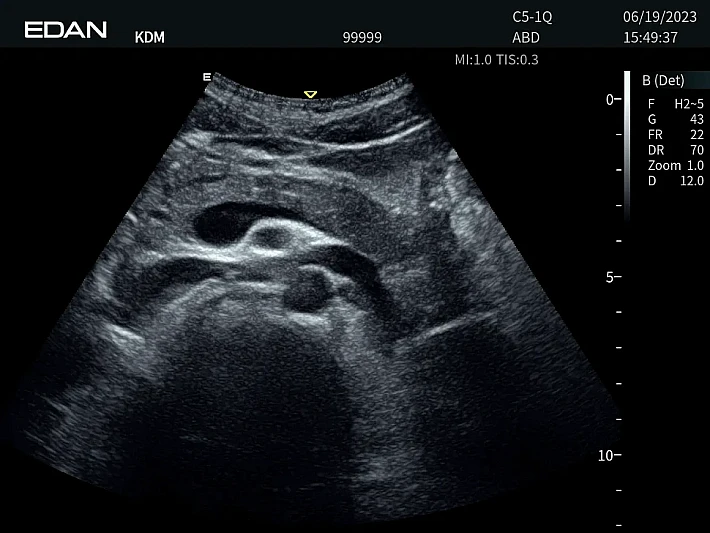

Медицинское оборудование и сервисное обслуживание